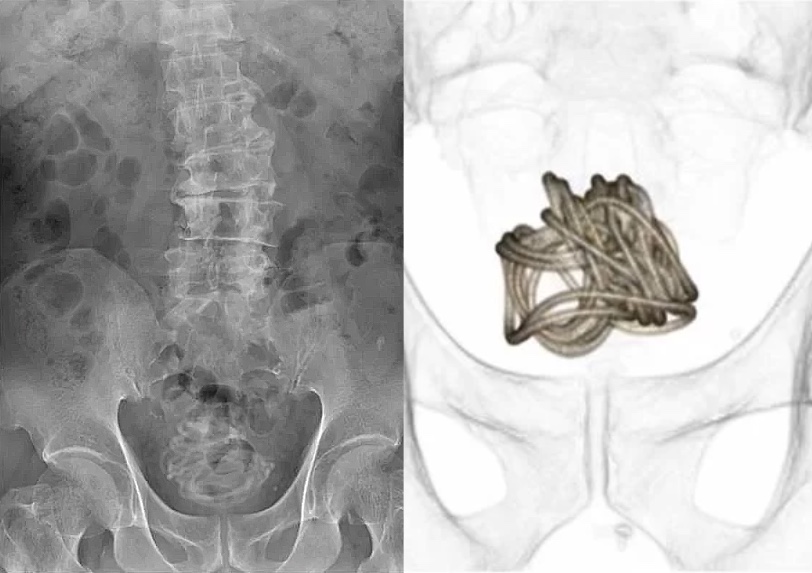

O homem foi até uma unidade hospitalar reclamando de dores no abdômen e com dificuldades para urinar. Ele fez um exame de imagem para verificar a origem do desconforto, então a equipe médica se assustou ao ver que a corda enrolada na bexiga do paciente. O paciente admitiu ter enfiado a corda pela uretra, mas não explicou o motivo.